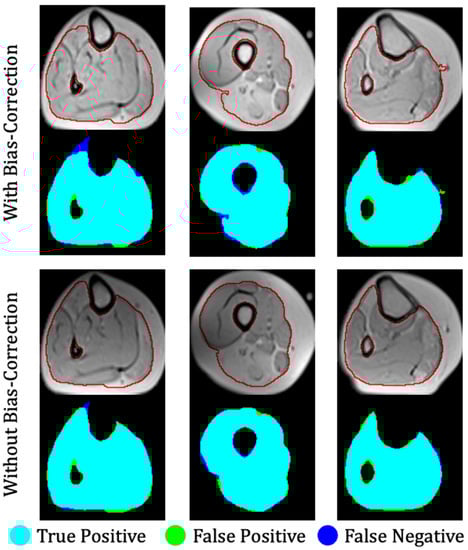

The proposed method was evaluated on the first dataset, which included 17 dysferlinopathy patients, with three test patients exhibiting mild, moderate, and severe levels of fat infiltration. Severity was evaluated on a slice-by-slice basis, where the pathology in each slice was considered mild, moderate, or severe according to whether IMAT was in the range 0–33%, 34–66%, or 67–100% of the entire muscle region, respectively. The results for the muscle region segmentation (stage 1) are presented in Table 1 and show a very high performance for the variety of inputs, proving the reliability and robustness of the method. The results are presented for mild, moderate, and severe patients as well as averaged over entire patient set. The results were also introduced using the leave-one-patient-out (LOPO) method on the 17 patients and demonstrated the generality and robustness of the method. The results in Table 1 show that the suggested method surpassed the ASeg technique at all disease severity levels, while the ASeg method performance deteriorated as the disease severity progresses, and our method preserved a high dice coefficient. Figure 7 shows the segmentation results where the muscle region was correctly segmented, even around the fascia lata, with a very small number of pixels that were wrongly classified (i.e., FPs and FNs). Accurate results were achieved, even in cases of strong fat infiltration.

The results of the different clustering methods explored are presented in Table 2 (stage 2 of the postprocessing pipeline). The proposed method—DCAETL with k-means—outperformed the competing methods in viable muscle Dice, IMAT Dice, accuracy, NMI, and ARI. In Figure 8, the visualization results of the clustering of viable muscle and IMAT are shown, the classification was shown only on the muscle region that was segmented in stage 1.

Figure 7. Three examples of segmentation of a calf anatomy. Left to right: mild, moderate, and severe levels of fat infiltration. Top: With bias field correction; bottom: without bias field correction. Manual segmentation contours are shown in red. Overlap between ground truth and the output of the fully convolutional network is color-coded to indicate regions of true positive, false positive, and false negative segmentation.

Figure 8. Three examples of FCN-based classification of thigh anatomy: (a) axial MR images of three different patients after applying the first stage of the proposed method and segmenting the muscle region; (b) ground truth of the intermuscular adipose tissue (IMAT) and viable muscle pixels within the muscle region (white: viable muscle: gray: IMAT pixels); (c) tissue classification using the suggested FCN processing.